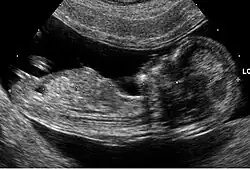

Ecografía obstétrico a las 12 semanas de gestación. Los marcadores ecográficos suelen realizarse en el primer trimestre, entre las semanas 11 y 14.

La ecografía genética o simplemente eco genético es un tipo de ultrasonido obstétrico que consiste en la valoración del feto para demostrar o descartar cualquier alteración anatómica o del estado de la salud del medio intrauterino reportando hallazgos o marcadores que pueden orientar en la identificación de fetos que tengan alteraciones cromosómicas.[1]​ La ecografía genética no tiene una precisión absoluta, de manera que una ecografía normal no garantiza que el bebé sea normal y hallazgos considerados anormales por un ecografista no garantiza que el bebé no sea normal.[1]

La ecografía genética se indica a pacientes embarazadas mayores de 35 años de edad, debido a que la edad materna avanzada predispone a la no disyunción cromosómica y por tal motivo se asocia al nacimiento de niños con cromosomopatías, particularmente trisomías 21, 18 y 13.[2]​ También se indican otros marcadores bioquímicos a partir de la semana 14 del embarazo, incluyendo los niveles séricos maternos de alfa-fetoproteína (AFP), para descartar trastornos cromosómicos en el feto.